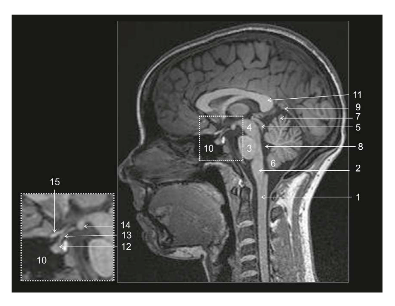

Coupe ?

Légende ?

Coupe ? Légende ?